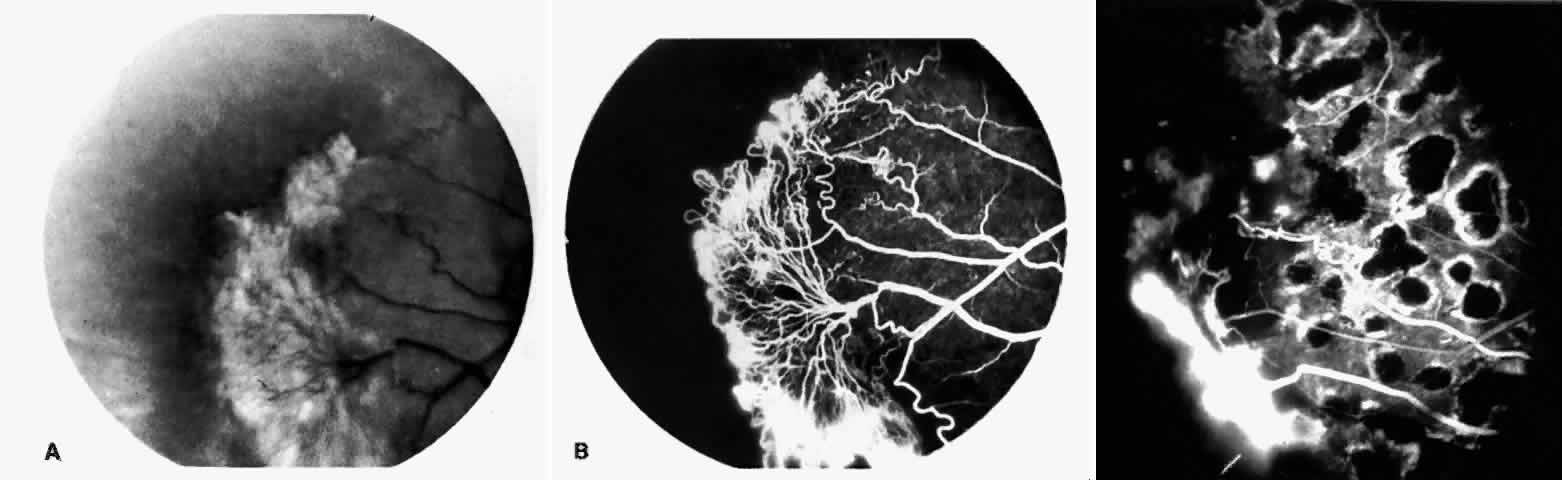

STAGE III: PRERETINAL NEOVASCULARIZATION (PROLIFERATIVE SICKLE RETINOPATHY). “Sea fan”-shaped neovascularization typically develops on the venular side of an arteriolar-venular anastomosis, mimicking the normal development of retinal capillaries (Fig. 24).125 A lowered oxygen tension and angiogenic factors released on the venular side may be the stimulus for neovascular growth.125,126 In most instances, the direction of growth is toward the ora serrata, from the perfused retina toward the nonperfused retina. Presumably, this represents an abortive attempt to revascularize the nonperfused retina, initiated by vasoproliferative factors.

Fig. 24. A. Photograph of the peripheral retina, demonstrating several small fibroglial membranes. B. Fluorescein angiogram corresponding to A, showing multiple arteriolar-venular anastomoses with early sea fan formation. C. Photograph of the same area 2 years later demonstrates more fibroglial membranes. D. Fluorescein angiogram corresponding to C shows new sea fans caused by an arteriolar-venular anastomosis (curved arrow). Large arrow (A through D) identifies corresponding arteriolar bifurcation.

The characteristic neovascular lesions of PSR are called sea fans because they resemble the marine invertebrate Gorgonia flabellum.70 They tend to occur more commonly in the temporal periphery, but they have been reported to occur in the temporal macula in the presence of extensive nonperfusion.130,133 Initially they grow on the surface of the retina, but they often become elevated into the vitreous and adhere to a partially detached posterior hyaloid.114 It may be difficult to visualize small sea fans ophthalmoscopically; however, fluorescein angiography clearly demonstrates leakage of dye into the vitreous (Fig. 25). The feeding arteriole is usually more tortuous than the draining venule (Fig. 26). Early on, the neovascular lesion is fed by a single arteriole and drained by a single venule, but with time, additional arterioles and venules become arborized within the lesion (Fig. 27).129 Growth of the sea fan often occurs circumferentially, rather than radiallyÜmh- 1Ý, toward the ora serrata. Progressive circumferential growth may lead to neovascular lesions extending around the entire periphery. As it matures, a white fibroglial mantle often covers the neovascular tissue (Color Plate 2B).

Fig. 25. Fluorescein angiogram of early proliferative sickle retinopathy arising from an arteriolar-venular anastomosis in an area of irregular peripheral capillary border. Note that this area of qualitatively abnormal peripheral capillary border is in the same eye with a qualitatively normal peripheral retinal vasculature, as demonstrated in Figure 23.

Fig. 26. A. Arterial filling phase of the fluorescein angiogram of a sea fan demonstrates tortuosity of the feeding arteriole. B. Early arteriolar-venular filling phase demonstrates straightening of the draining venule. Note that this sea fan is adjacent to the qualitatively normal peripheral retinal vasculature demonstrated in Figure 23.

Fig. 27. A. Photograph of sea fan neovascularization with hemorrhages at the margins and a white line demarcating perfused and nonperfused retina. B. Fluorescein angiogram shows multiple feeding arterioles and draining venules.

PSR is associated with the severe vision-threatening sequelae of sickle cell disease: vitreous hemorrhage (stage IV) and retinal detachment (stage V). These stages are believed to result from transudation of blood components into the vitreous through the incompetent neovascular tissue (Fig. 28). Vitreous fluorophotometry has quantified the leakage from the peripheral neovascularization.134 This leads to premature syneresis and collapse of the vitreous, inducing tractional forces on the retina that lead to vitreous hemorrhage, retinal tears, and tractional and rhegmatogenous retinal detachment. In rare cases, an exudative detachment may occur.